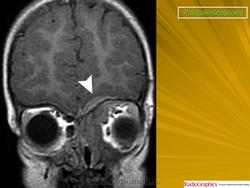

Рабдомиосаркома — чрезвычайно агрессивная опухоль орбиты, является наиболее частой причиной злокачественного роста в орбите у детей. Мальчики болеют почти в 2 раза чаще. Источником роста рабдомиосаркомы являются клетки скелетных мышц. Выделены три типа опухоли: эмбриональный, альвеолярный и плеоморфный, или дифференцированный. Последний тип встречается редко. У детей до 5 лет чаще развивается эмбриональный тип опухоли, после 5 лет — альвеолярный. Как правило, рабдомиосаркома состоит из элементов нескольких типов (смешанный вариант). Точный диагноз можно установить только на основании результатов электронной микроскопии.

Излюбленная локализация опухоли — верхневнутренний квадрант орбиты, поэтому в процесс рано вовлекаются мышца, поднимающая верхнее веко, и верхняя прямая мышца. Птоз, ограничение движений глаза, смещение его книзу и книзу кнутри — это первые признаки, на которые обращают внимание как сами больные, так и окружающие лица. У детей экзофтальм или смещение глаза при локализации опухоли в переднем отделе орбиты развивается в течение нескольких недель (рис. 20.23, а). У взрослых опухоль растет медленнее, в течение нескольких месяцев. Быстрое увеличение экзофтальма сопровождается появлением застойных изменений в эписклеральных венах, глазная щель полностью не смыкается, отмечаются инфильтраты на роговице и ее изъязвление. На глазном дне — застойный диск зрительного нерва. Первично развиваясь вблизи верхневнутренней стенки орбиты, опухоль быстро разрушает прилежащую тонкую костную стенку, прорастает в полость носа, вызывая носовые кровотечения. Ультразвуковое сканирование, компьютерная томография, термография и тонкоигольная аспирационная биопсия — это оптимальный диагностический комплекс инструментальных методов исследования при рабдомиосаркоме (рис. 20.23, б). Лечение комбинированное. Протокол лечения предусматривает предварительное проведение полихимиотерапии в течение 2 нед, после чего проводят наружное облучение орбиты. После комбинированного лечения более 3 лет живут 71 % больных.